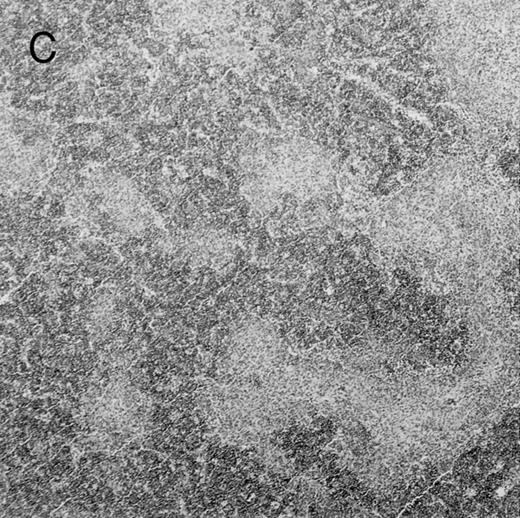

Histologic findings. Organs were collected at different times after BMT and tissue sections were stained with hematoxylin and eosin. Original magnifications for spleen (left) and liver (right) are ×40 and ×100, respectively. (A) B6 mice receiving FVB BM plus EpTK T cells. (B) Control group receiving BM only.

(C) B6 mice receiving FVB BM plus EpΔTK T cells and treated with GCV. (D) B6 mice receiving FVB BM plus EpΔTK T cells, treated with GCV, and developing a late onset GVHD (day 54).

Protection from GVHD was slightly less efficient in the group receiving EpΔTK CD3+ T cells. The survival rate was 79% at day 60 and 67% at day 120 (Fig 2B). However, two different outcomes must be distinguished. On the one hand, a majority of mice behaved as GCV-treated animals receiving EpTK T cells. They were apparently healthy, presented no skin lesions during a 120-day observation period, and showed complete donor-type hematologic reconstitution. There were no histological signs of GVHD in the spleen or liver (Fig 4C).